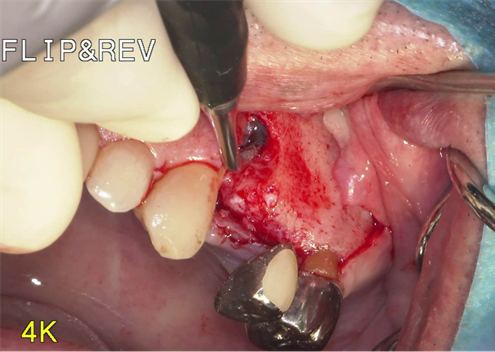

①歯槽頂よりサイナス

リフトを行いました。

②血液成分とカルシウム材料により骨造成をしました。

③ガイデッドサージェリーにてインプラント埋入しました。

④計画通りの埋入が出来ました。